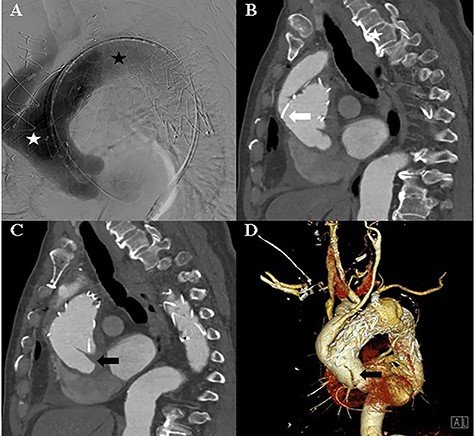

The TEVAR was performed 14 days after the debranching surgery. Under local anaesthesia, a Safari wire was placed in the left ventricle cavity. A Medtronic Valiant Thoracic Stent Graft (46 mm × 46 mm × 200 mm) was implanted in the ascending thoracic aorta and aortic arch, and a second Medtronic Valiant Thoracic Stent Graft (42 mm × 42 mm × 200 mm) was implanted in the aortic arch and descending thoracic aorta. The left subclavian artery was plugged with an Amplatzer Vascular Plug (16 mm) (Fig. 2).

A: Aortic angiography during TEVAR shows the thoracic graft implanted in the ascending thoracic aorta and aortic arch (white asterisk) and the thoracic graft implanted in the aortic arch and descending thoracic aorta (black asterisk). B: Computed tomography of the post-TEVAR shows the placed thoracic graft (white arrow). C and D: Computed tomography of the post-TEVAR shows the intimal dissecting flap at the proximal ascending aorta.

The patient remained asymptomatic with stable vital signs. A scheduled computed tomography was performed after 1 week. Computed tomography revealed a newly localized intimal dissecting flap at the proximal ascending aorta, which was located proximally, extending to the ostia of the right coronary artery. The patient underwent an emergency open repair operation. Circulatory arrest was established at a rectal temperature of 20°C, and cerebral perfusion was accomplished through the 18-mm graft cannula and left femoral artery cannulation. During gross examination, the 18-mm graft was seen detached from the ascending aorta, which was opened longitudinally, and an intimal tearing site was identified (Fig. 3). The dissection occurred transversely at the proximal stented site and was extended up to the sinotubular junction around the left coronary sinus and near the right coronary orifice in the right coronary and non-coronary sinuses. A Gelweave 28-mm straight graft was used, which was connected to the proximal aorta and reinforced with the double sandwich technique (Fig. 3). The distal anastomosis was performed, including a proximal resected valiant stent graft and the patient’s native aorta with a Teflon felt by sandwich technique. After the operation, the patient remained asymptomatic.